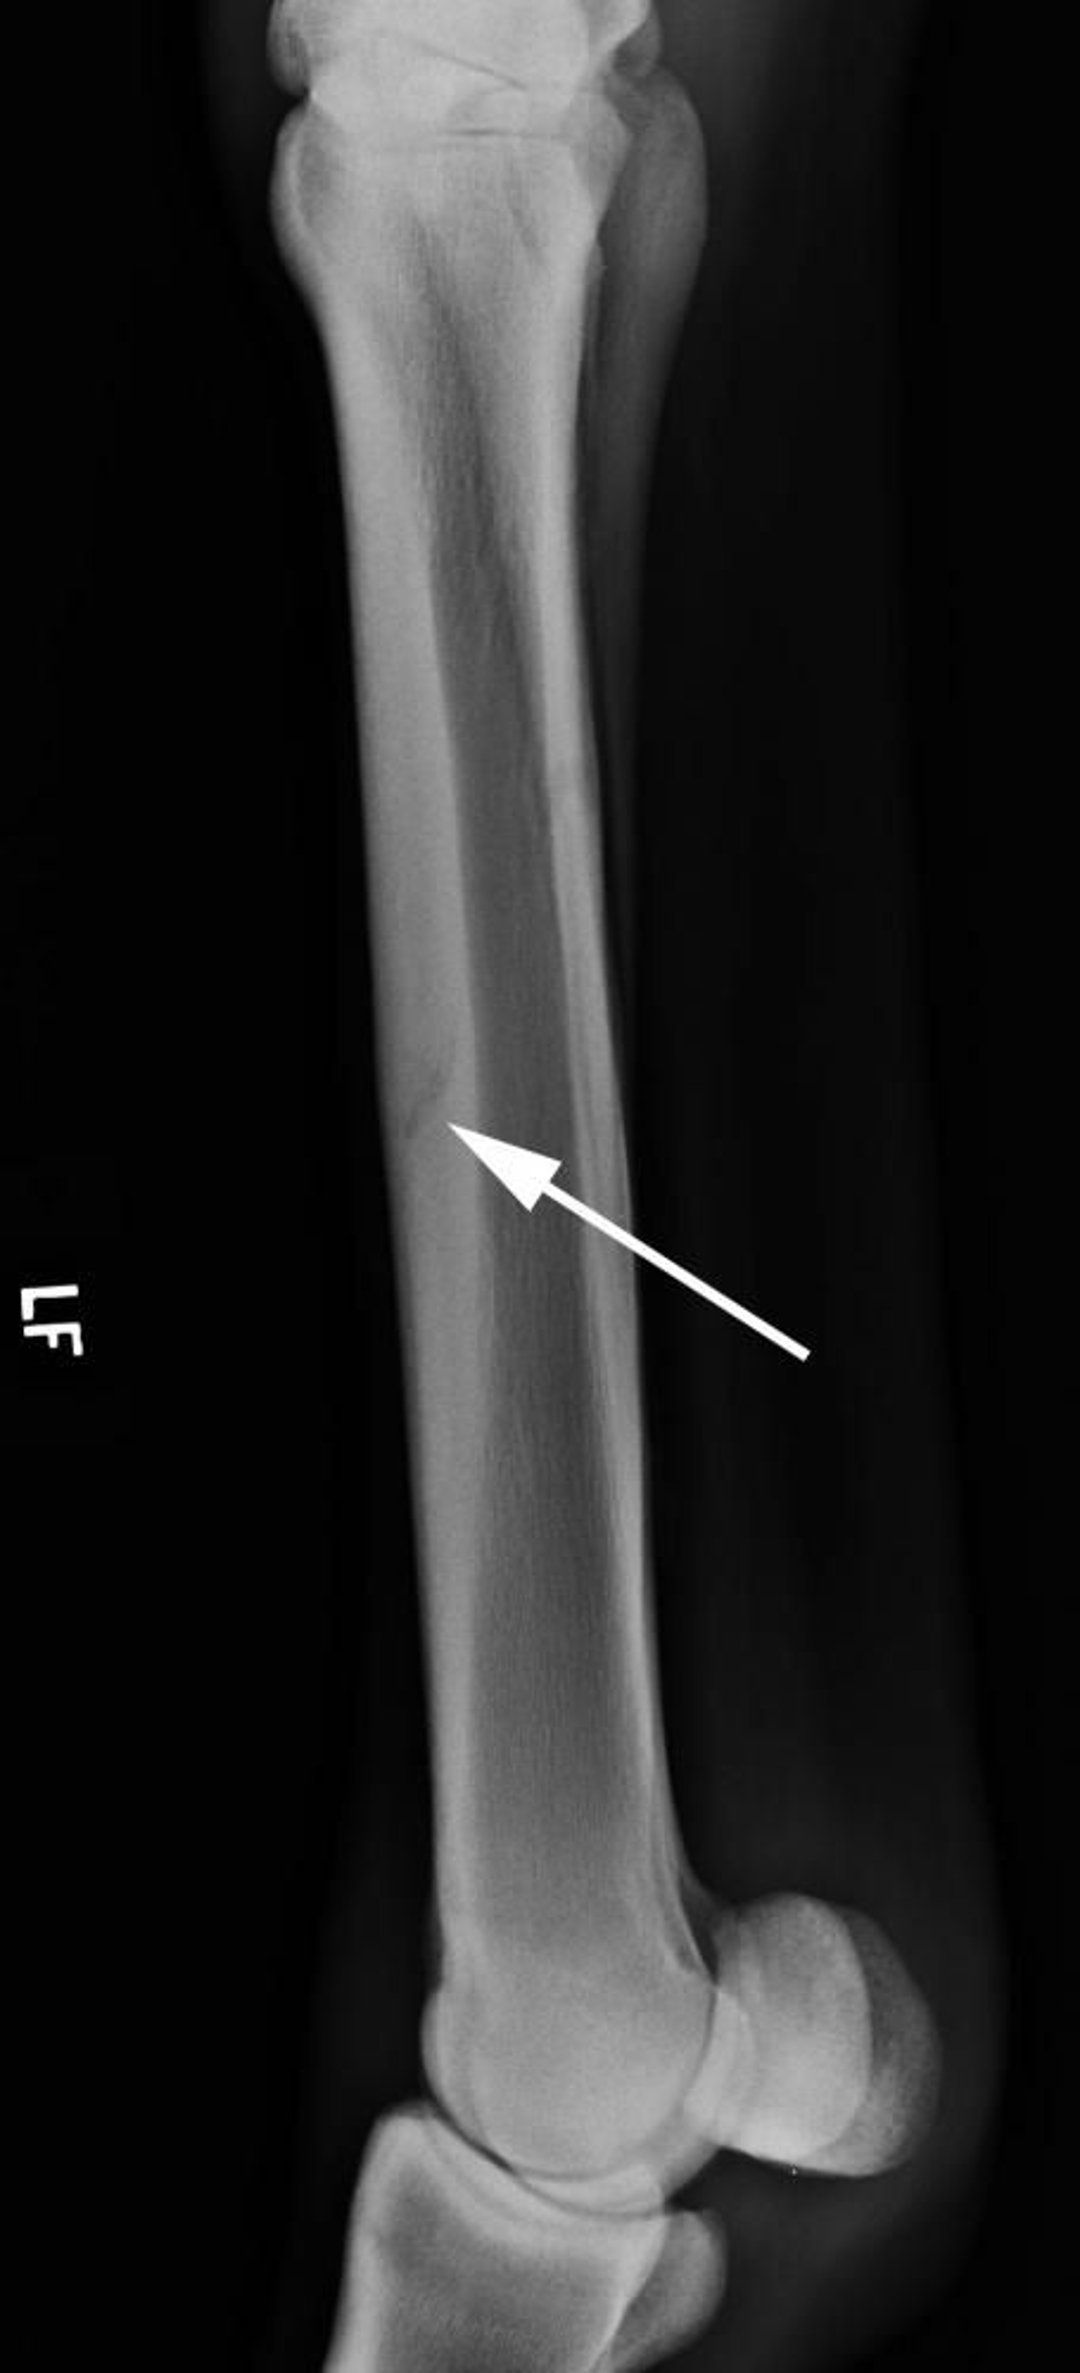

Lateral radiograph showing a typical dorsal cortical stress fracture of the third metacarpus (arrow) in a racing Thoroughbred.